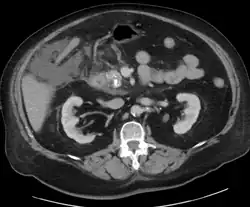

A contrast-enhanced CT scan is usually performed more than 48 hours after the onset of pain to evaluate for pancreatic necrosis and extrapancreatic fluid as well as predict the severity of the disease. CT scanning earlier can be falsely reassuring.[34]